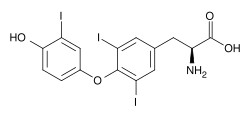

| Triiodothyronine (T3, pictured) and thyroxine (T4) are both forms of thyroid hormone. | |